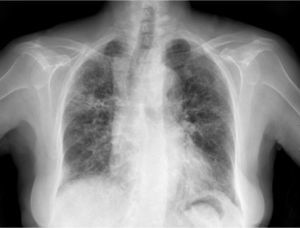

Clinical CaseThe patient is an 83-year-old woman with a history of hypertension treated with amlodipine 5mg/day, chronic kidney disease stage III, secondary to nephrosclerosis (GFR 45ml/min) and chronic treatment of polymyalgia rheumatica with methotrexate 15mg/week, for 4 years approximately. In recent years she has shown good clinical and analytical stability, not requiring steroid therapy or adjustments to her regular medication. Six weeks before admission she progressively presented fatigue, dyspnea, cough, and weight loss of 5kg. She had no fever, joint pain or muscle weakness. On admission, dyspnea at rest was observed with a baseline oxygen saturation of 90%, pulmonary auscultation showed bilateral fine crackles, with no palpable lymphadenopathy or organ enlargement, elevated erythrocyte sedimentation rate of 69mm C-reactive protein 3.5mg/dl and a chest X-ray which highlighted a diffuse and asymmetric bilateral reticular infiltrate with peripheral involvement, worse on the bases and on the right upper lobe (Fig. 1). After making a differential diagnosis of subacute lung disease in the context of methotrexate use, our main approach was to discontinue treatment, start steroids intravenously 48mg/day of methylprednisolone, and support measures, without clear improvement. A high resolution chest CT scan (HRCT) was performed, showing patched interstitial thickening of peripheral predominance in the lung bases and small nonspecific mediastinal lymphadenopathy (Fig. 2). The pulmonary function tests showed forced spirometry values in the low limit of normal, with a forced vital capacity (FVC) 1340ml (82%), a volume of expiratory flow after one second (FEV1) of 1130ml (88%) and an FEV1/FVC ratio of 84%, associated with a severe decrease in lung diffusion of carbon monoxide (DLCO) of 33% and corrected for an alveolar volume (KCO) of 54%. In the rest of the complementary tests, no changes were seen in the blood count, serology for atypical pathogens, the study of tumor markers, blood cultures, the serial study of sputum or the Mantoux/Booster test, so a bronchoscopy was performed with bronchoalveolar lavage (BAL) and led to a positive result in polymerase chain reaction (PCR) testing for CMV associated with an increased rate of CD4/CD8 lymphocytes 3.47, with the rest of the study for common germs, tuberculosis, P. jiroveci and fungi being negative. The microbiological study detected IgG (+), IgM (−) for CMV and CMV viral load in plasma (+), so treatment was initiated intravenously, adjusted for renal function, with ganciclovir 300mg/12h for 14 days, then changing to valganciclovir 900mg/12h orally for 14 days, with good tolerance and clinical response, with improvement in radiological, serological (CMV viral load undetectable) and respiratory function parameters (57.52% DLCO, KCO 80.90%, FVC 1950ml [119%] and FEV1 of 1680ml [130%]).